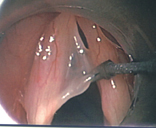

喉部顯微手術的過程其實非常簡單。首先,為了減少手術過程中的不適,患者需要接受短暫的全身麻醉。之後醫師會使用硬式的『喉直達鏡』(圖一),將會厭軟骨挑起並固定支撐後即可清楚的看到聲帶的全貌。跟一般門診使用的喉部內視鏡比起來(圖二,象牙白色直直的兩條即為聲帶),經過手術顯微鏡放大4-10倍之後,所有的聲帶病變均無所遁形,無論是聲帶表層常見的長繭(圖三,雙側聲帶長繭),或是聲帶息肉,都可以藉由特製的精細長柄器械,在顯微鏡下操作切除(圖四),以恢復聲帶平整的外觀。

圖三、雙側聲帶均有長繭造成聲音時相互碰撞而沙啞

圖四、喉顯微手術切除聲帶繭的狀況